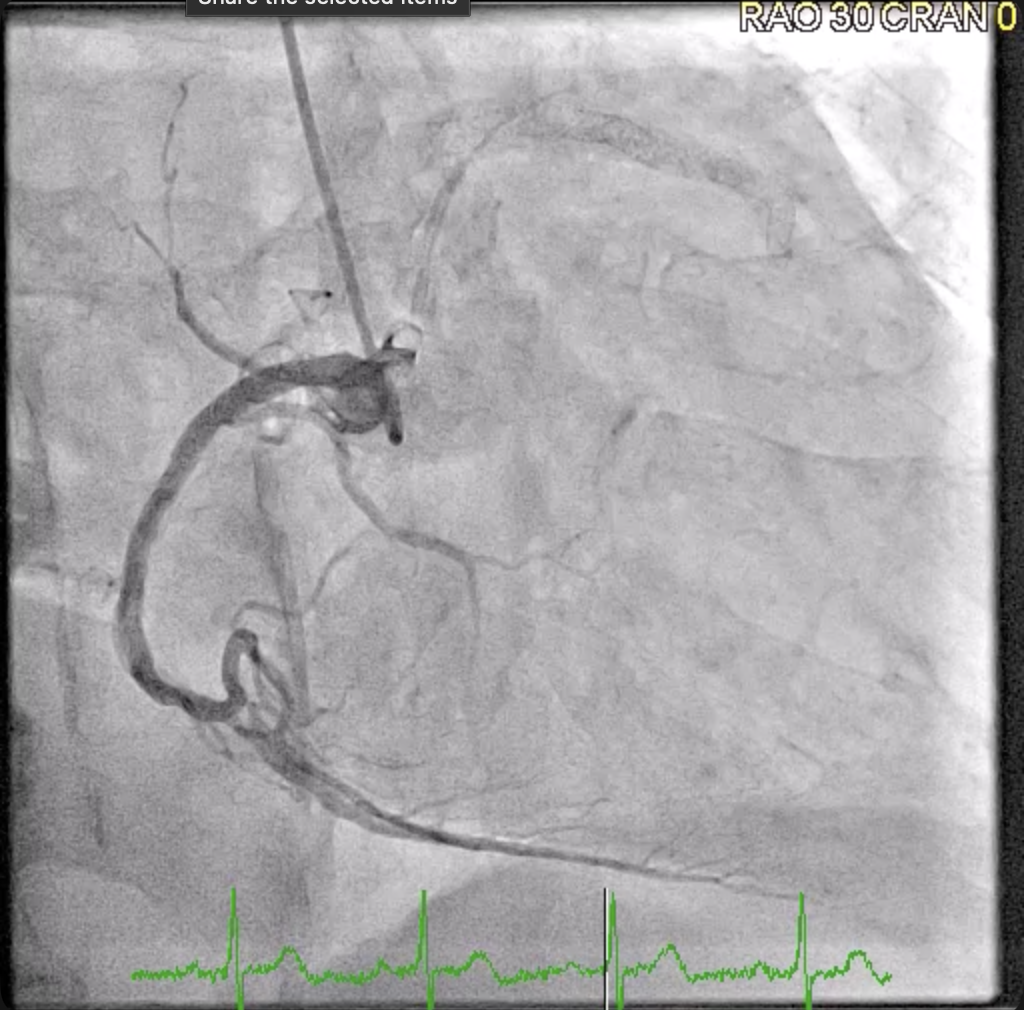

Relevant Catheterization Findings

Coronary angiogram showed the LM as a good-sized vessel with luminal irregularities. The LAD is a good-sized Type III vessel with a 30% late in-stent restenosis at the proximal to mid segment. The D1 is a fair-sized vessel with a 40% proximal stenosis. The LCX is a good-sized non-dominant vessel with a 99% ostioproximal stenosis. The obtuse marginal branches are fair-sized with luminal irregularities. The RCA is a good-sized dominant vessel with a patent proximal stent and a 30% mid stenosis.

A 7F EBU 3.5 guide was used and an Asahi Sion Blue (Asahi Intecc, Japan) wire distalized into the LAD and a Sion wire crossed through the previous LM to LAD stent struts and distalized into LCX. After opening the stent struts, kissing balloon inflation (KBI) using a 3.5 mm balloon in the LM to LAD and a 2.5 mm balloon in the LM to LCX was done. IVUS showed LCX MLA of 3.48 mm2 and LAD MLA of 6.55 mm2. IVL in the LCX was done using a 3.0 mm IVL balloon for 8 cycles then in the LAD using a 4.0 mm IVL balloon for 5 cycles. A Xience Sierra (Abbott Vascular, USA) 3.0 mm x 33 mm stent was deployed at the LM to LCX then a POT at the LM. A Sion Blue was crossed through the LM to LCX stent struts and distalized into the LAD. Another KBI was done then a 4.0 mm DCB was deployed at the ostioproximal LAD for 1 minute. There was noted difficulty advancing the IVUS catheter past the proximal stent edge at the LM through the LM to LCX guidewire. IVUS of the LAD showed abluminal rewiring of the LAD stent resulting in an intraluminal jailing of the LCX wire and a stented double lumen LM. To resolve this, a Sion Blue was crossed through the LM to LCX stent struts through an Asahi Sasuke (Asahi Intecc, Japan) double lumen microcatheter and distalized into the LAD. Inflations with a 3.0 mm balloon at the LM to LCX were done followed by another KBI and finally POT at the LM. Final IVUS showed good stent expansion and apposition, LM MSA of 13.20 mm2, LAD MSA of 9.69 mm2, and LCX MSA of 6.23 mm2.

Final angiography revealed TIMI III flow with no residual stenosis, dissection, or perforation. The patient tolerated the procedure well without hemodynamic instability or other complications. He was transferred to the telemetry unit and completed cardiac rehabilitation prior to discharge. In consideration of the patient's late restenosis only 5 months after his initial PCI, intravascular lithotripsy, stenting of the LM to LCX, and DCB of the LAD were effective treatments to address the restenosis. In addition, utilization of IVUS and a double lumen microcatheter were effective strategies to resolve an abluminal wiring and double lumen stent complication in the LM bifurcation.